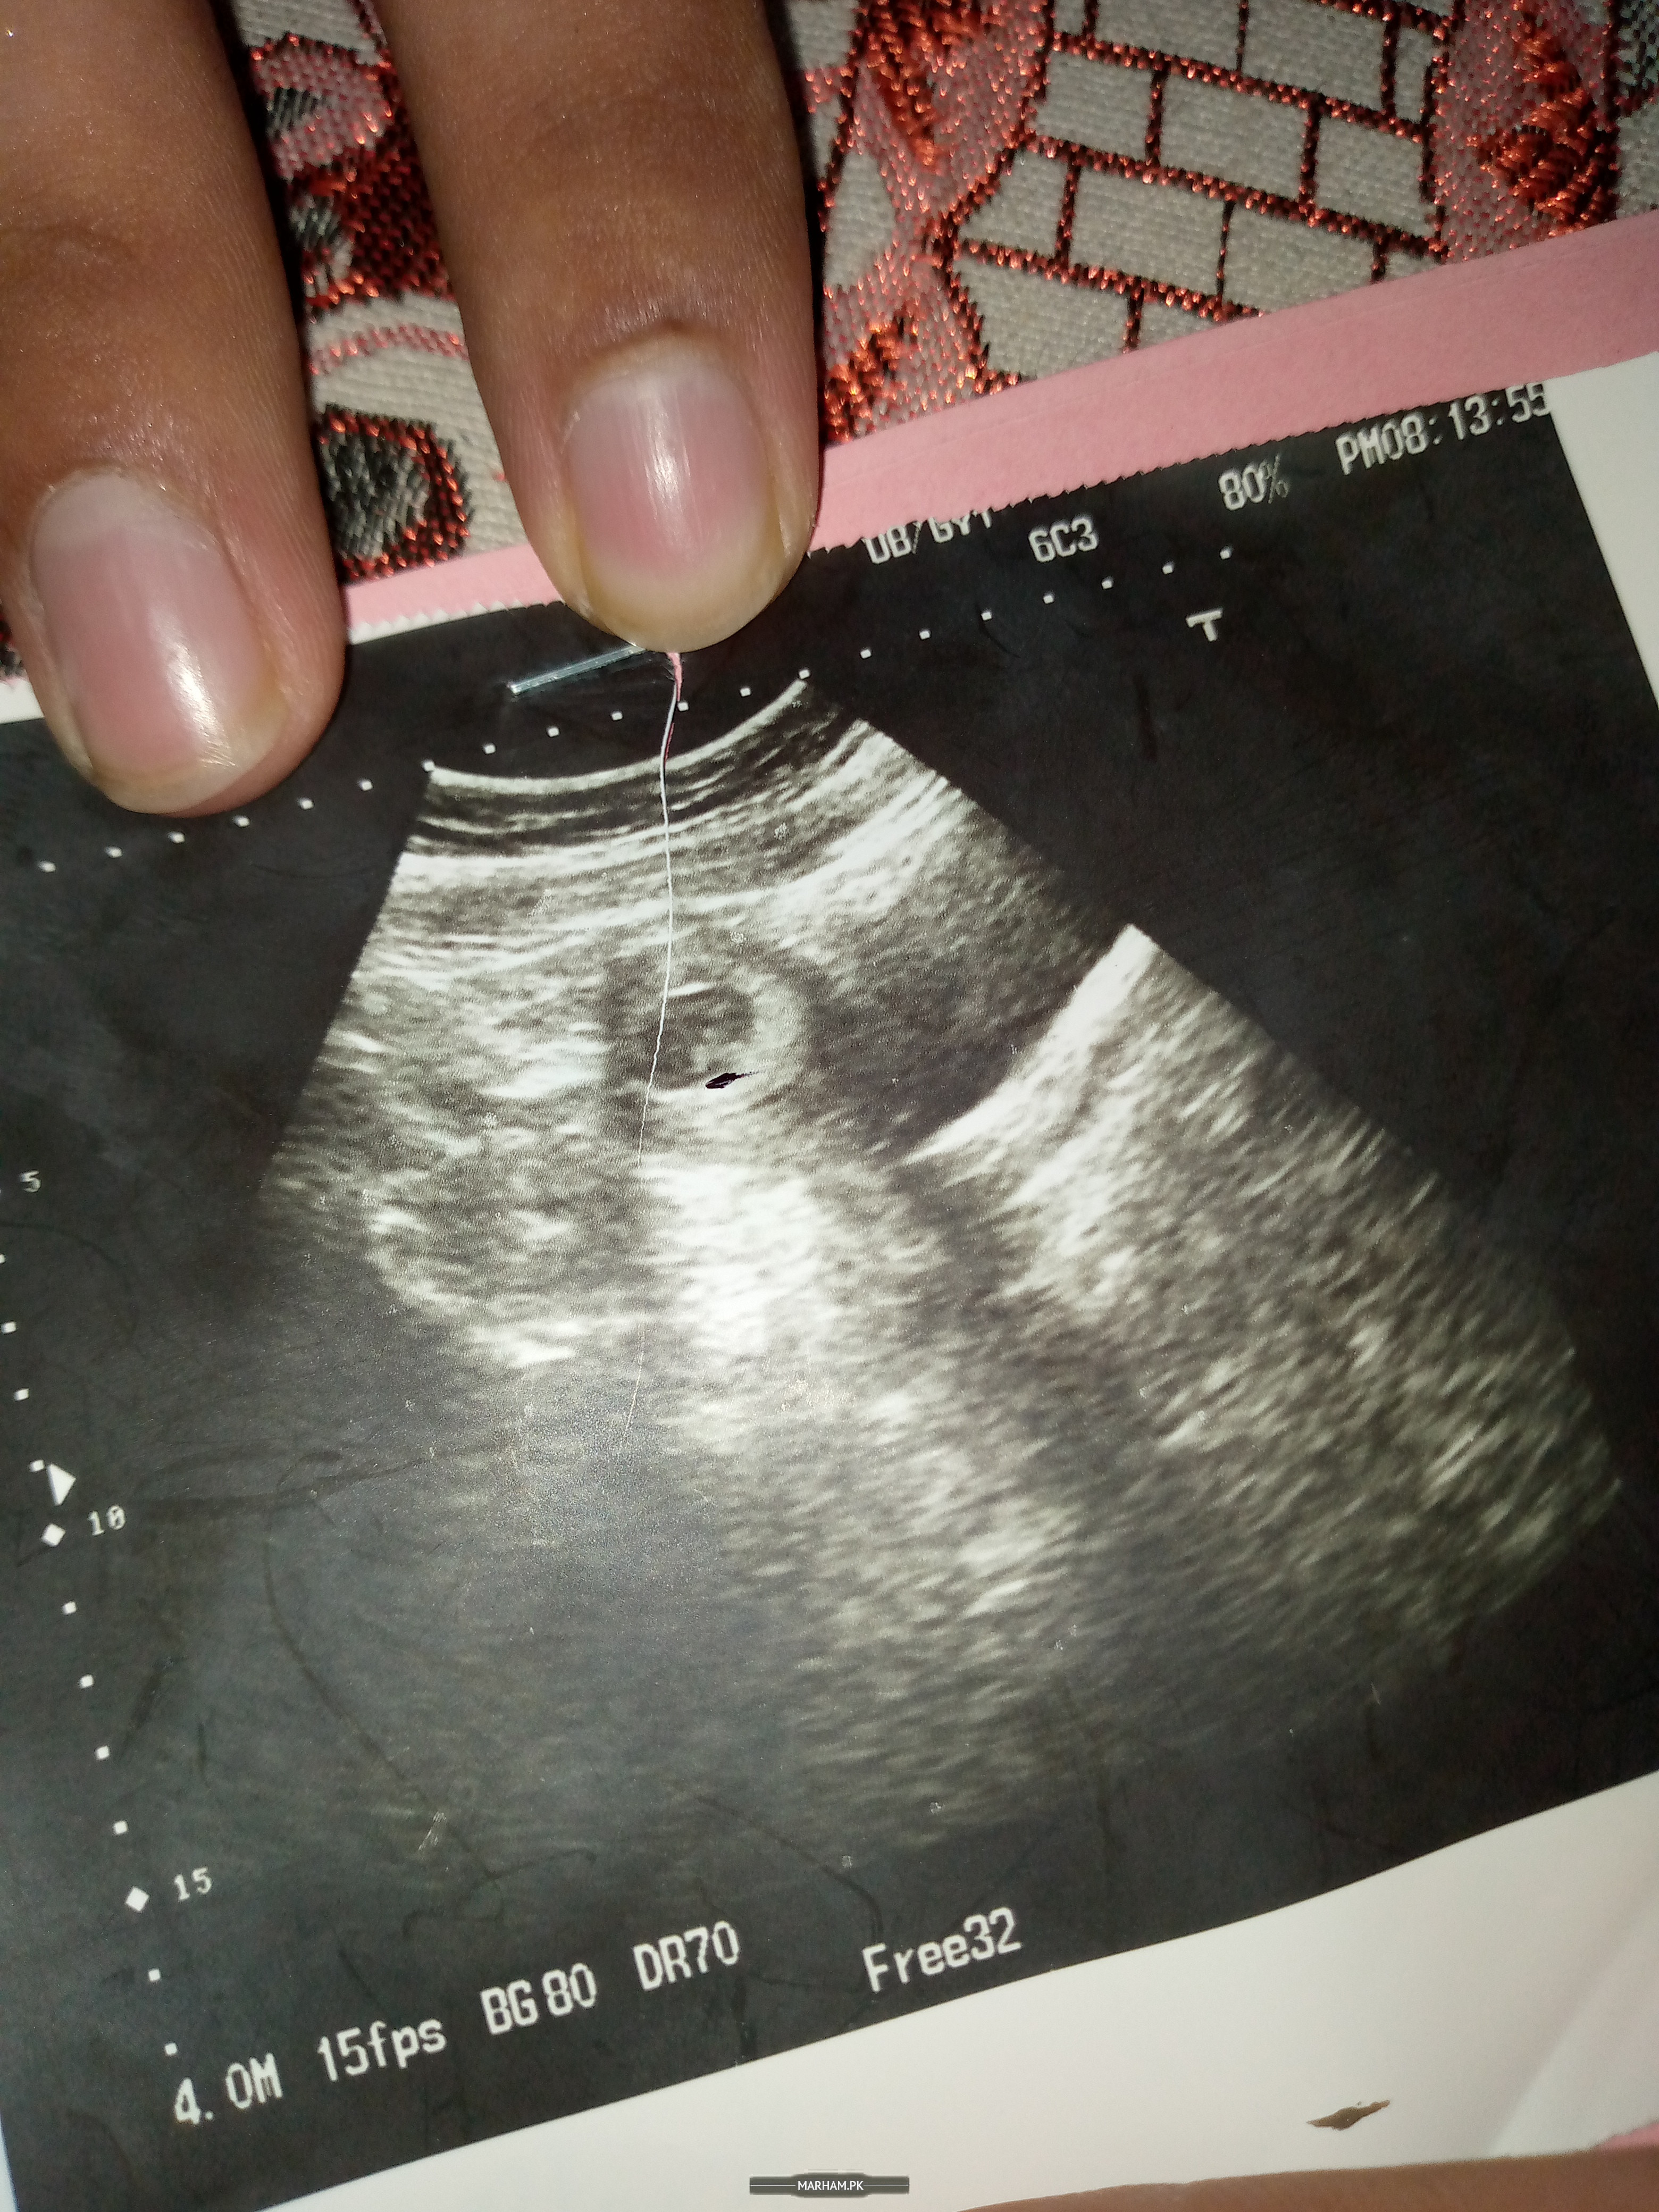

Salam mam ,, meri pregnency ko 10 weeks ho gy hn par baby ki heartbeat nhi hy or growth 1.9 crl hy Kya me abort kra lu ya wait kru?

It is missed miscarriage..u need to go to hospital for D&c

Please share the report of last ultrasound

Share that report with date

9/8/21

Member of Marham-Forum

Is ki report kidher hai ?

mjhy to bus yhi reports de Hain doctor ny